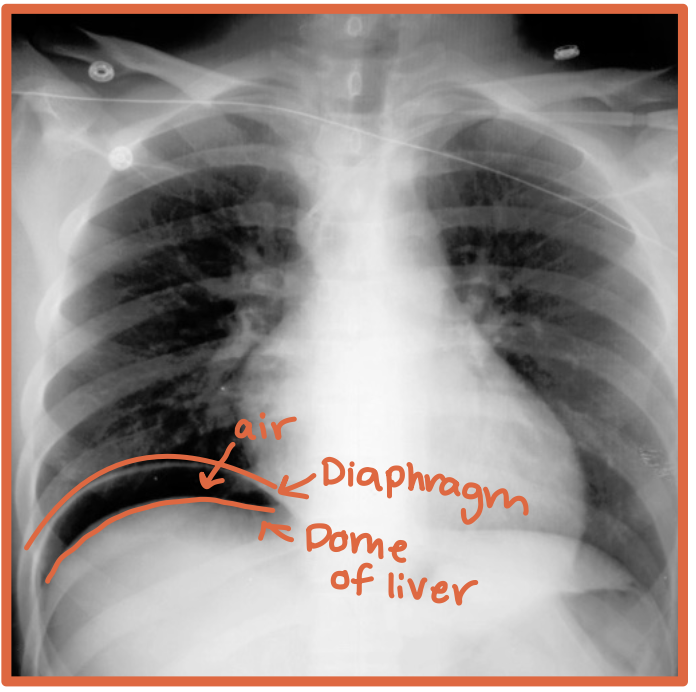

What is the diaphragm?

A thin curved sheet of muscle separating the thoracic and abdominal cavities

Where is the liver located relative to the hemidiaphragms?

Under the right hemidiaphragm

R + Liver = River

Where is the stomach located relative to the hemidiaphragms?

Under the left hemidiaphragm

Stomach took an L

What does free air below the hemidiaphragms on imaging mean?

Free air outside the bowel in the peritoneal cavity, usually suggesting bowel perforation

What gas is normal to see in the abdomen on imaging?

Gastric or bowel gas inside the GI tract